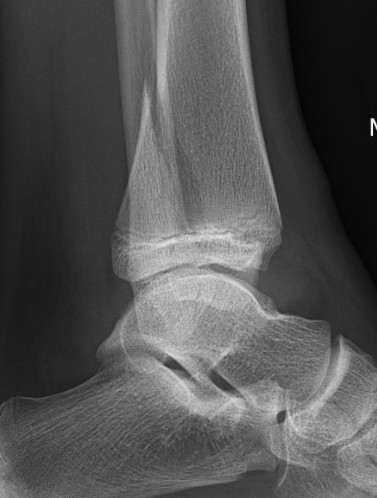

| SH III distal tibia / Tillaux | Triplanar fracture |

![]() |

| Low risk growth arrest / physeal bar | 1% growth arrest as adolescent patients |